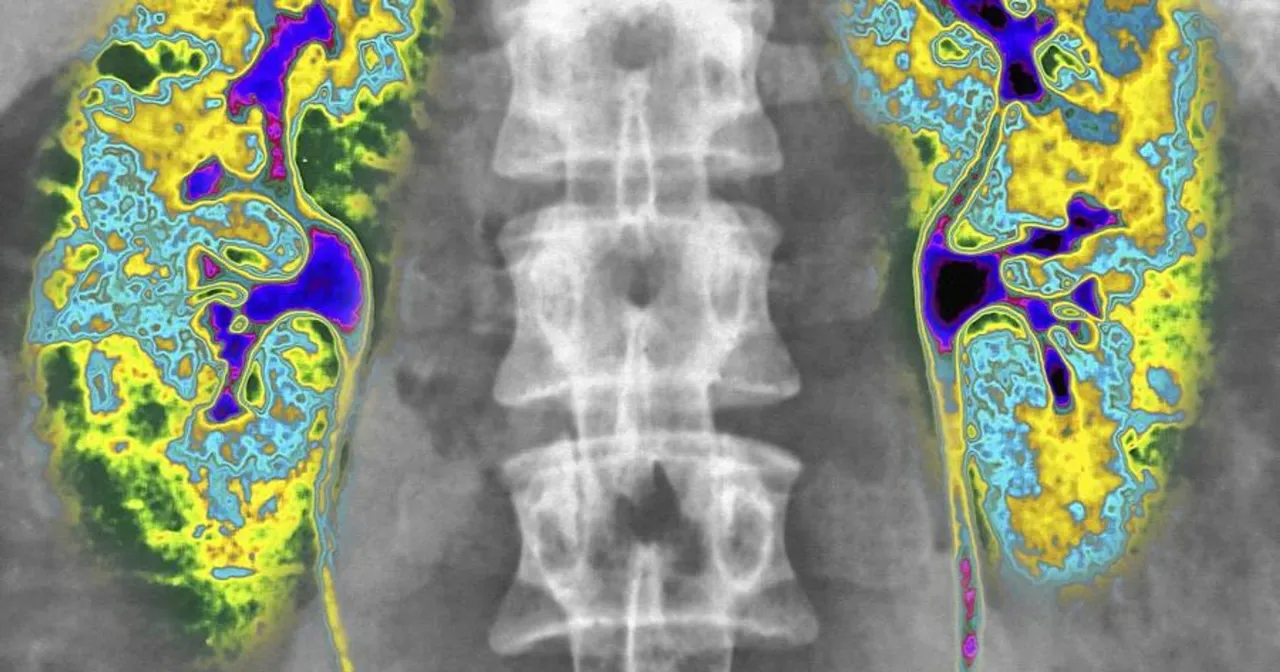

Po podaniu radioznacznika, specjalna aparatura zwana gammkamerą, rejestruje emitowane przez niego promieniowanie. Na podstawie tych danych tworzony jest obraz całego szkieletu, czyli tak zwany scyntygram. Dzięki temu możemy "zobaczyć" zmiany w kościach, często jeszcze zanim dadzą one o sobie znać w inny sposób, co jest kluczowe dla wczesnej diagnostyki i skutecznego leczenia. To właśnie ta zdolność do wczesnego wykrywania sprawia, że scyntygrafia jest tak cenionym narzędziem.

Najbardziej zaawansowaną formą jest scyntygrafia SPECT/CT. To połączenie scyntygrafii (SPECT Single Photon Emission Computed Tomography) z tomografią komputerową (CT). Dzięki temu uzyskujemy nie tylko obrazy funkcjonalne (aktywność metaboliczna), ale także precyzyjne obrazy anatomiczne w trzech wymiarach. Pozwala to na dokładne umiejscowienie zmian i ich relację do otaczających struktur, co jest nieocenione w skomplikowanych przypadkach.